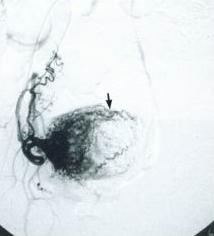

輸卵管良性腫瘤診斷查體:腹部稍膨隆,觸及左下腹有一個約13cm×10cm×10cm囊實性腫物,壓痛(±),表面光滑,稍活動,與周圍組織無粘連。婦科檢查:外陰已婚已產型,陰道通暢,宮頸肥大並見一約2cm×2cm×1cm那氏囊腫,子宮後位,正常大小,表面光滑,左側附屬檔案區觸及一個約13cm×12cm×10cm囊實性腫物,壓痛(±),表面光滑,邊界清楚,稍活動,與周圍組織無粘連,右側附屬檔案區未觸及異常,分泌物色黃、量中、有味。

婦科彩超:子宮前位,大小、形態正常。盆腔內探及13.3cm×9.8cm×12.6cm囊性光團,形態規則,界限清,其內為黏稠液體及較多絮狀略強回聲。

入院後診斷為“卵巢腫瘤”,於6月27日行剖腹探查術。術中見:大網膜粘於紫黑色腫瘤表面,左側輸卵管增大約13cm×12cm×10cm,呈紫黑色,表面無破潰,有一細長蒂,扭轉4周1440°,通過蒂腫瘤與左側卵巢緊鄰,左側卵巢大小、形態正常;右側輸卵管及右側卵巢正常,子宮大小及形態正常。

術中診斷:左側輸卵管腫瘤,行左側輸卵管切除術。術中快速病理為:纖維囊壁,內皮脫落伴退變壞死。術後病理:單純性囊腫,壁出血、水腫。術後患者恢復良好,按期出院。